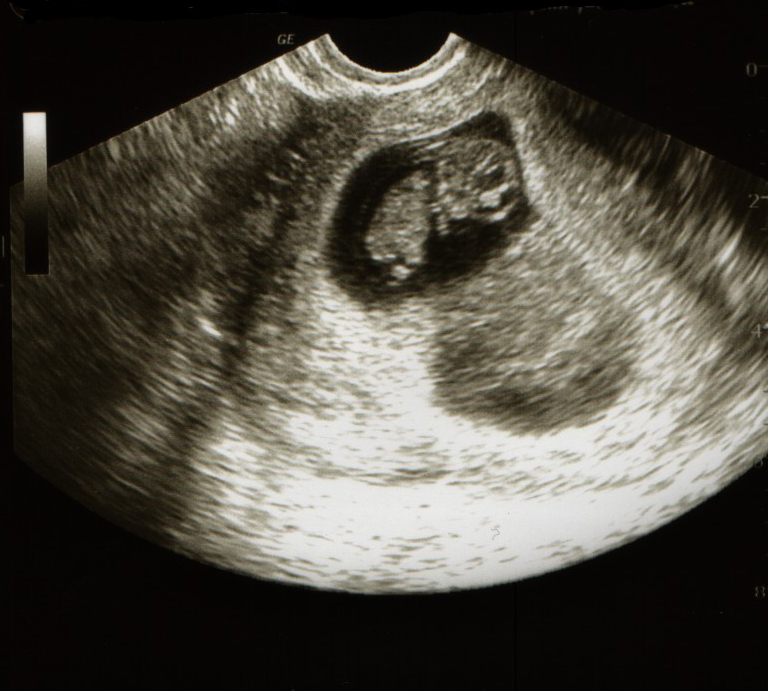

Развитие эмбриона на 8 неделе беременности